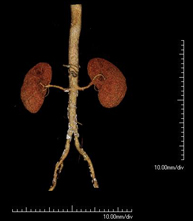

- Abdominal aorta CT angiography

A non-invasive diagnostic test that involves studying the abdominal aorta by obtaining high-definition anatomical images using CT (computed tomography) equipment and iodinated contrast. With the aid of workstations specialised for arterial studies, the image quality supports 2D and 3D reconstructions. It is indicated in patients with vascular disease (atherosclerosis), aortic aneurysms, abdominal pain of possible vascular origin, pre-surgical studies of lesions adjacent to the abdominal aorta as a vascular ‘map’, etc. Information obtained non-invasively is indispensable for patients requiring percutaneous or surgical processing. In patients who only require tracking of vascular lesions, this technique is the non-invasive technique of choice, together with MRI angiography.

- Renal artery CT angiography

A non-invasive diagnostic test that involves studying the renal arteries by obtaining high-definition anatomical images using CT (computed tomography) equipment and iodinated contrast. With the aid of workstations specialised for arterial studies, the image quality supports 2D and 3D reconstructions. This test is recommended, for example, in patients suffering from refractory hypertension that does not respond to processing, in patients with kidney damage in order to obtain a pre-surgical ‘vascular’ map, etc.

- Aortoiliac CT angiography

A non-invasive diagnostic test that involves examining the iliac arteries and abdominal aorta, obtaining high-definition anatomical images using CT (computed tomography) equipment and iodinated contrast dye. With the aid of workstations specialised for arterial studies, the image quality supports 2D and 3D reconstructions. This test is particularly recommended as a pre-surgical study (vascular map) prior to percutaneous or surgical interventions on the abdominal aorta, as a complementary study in patients with lower limb ischaemia, etc.

- Lower leg arterial CT angiography

Non-invasive diagnostic test consisting of a vascular study of the aorto-iliac sector and the arterial vessels of both lower extremities, obtaining high-definition anatomical images using state-of-the-art multidetector CT equipment and iodinated contrast. With the aid of workstations specialised for arterial studies, the image quality supports 2D and 3D reconstructions.